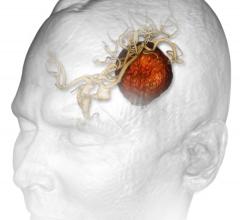

March 7, 2016 — Elekta announced that its Leksell Gamma Knife Icon stereotactic radiosurgery (SRS) system was used for ...